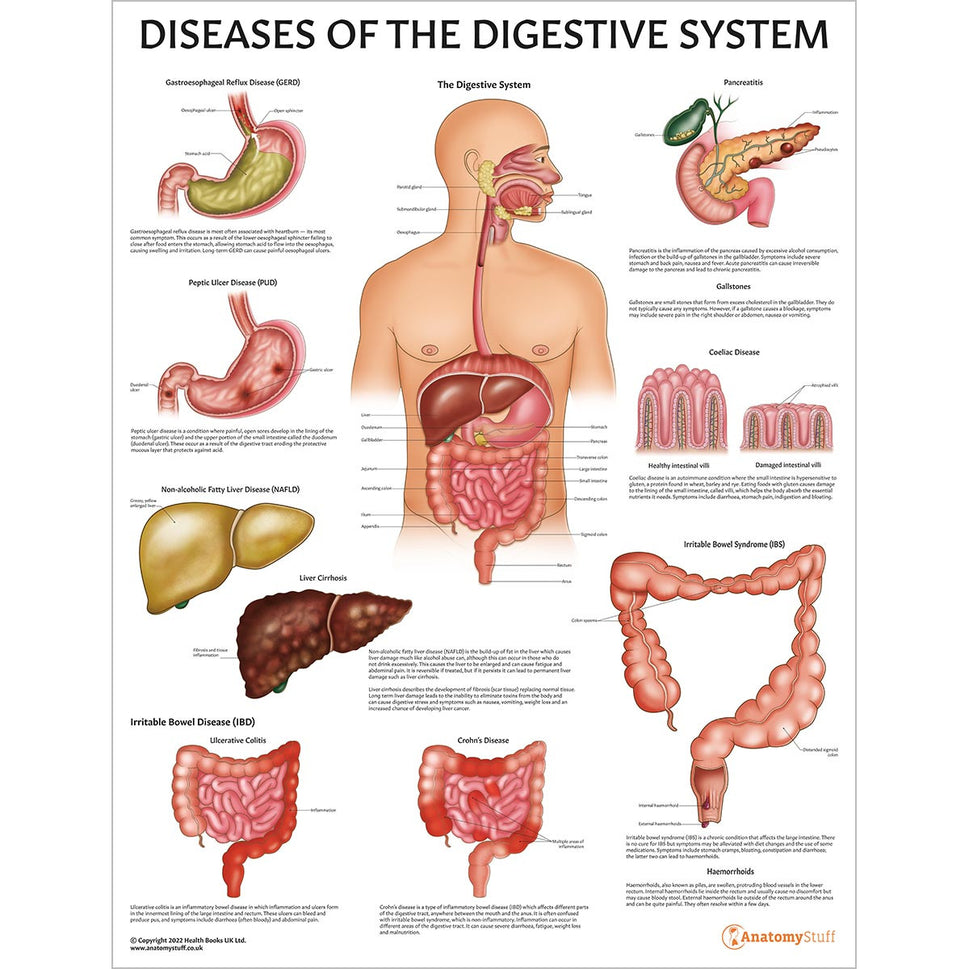

Enhance medical education with our collection of digestive system anatomical models including the stomach, liver, gallbladder, pancreas & colon models. Discover the anatomy of healthy organs as well as common gastrointestinal diseases such as stomach ulcers, gallstones and liver cirrhosis. Our digestive system anatomy posters are ideal for study and patient education.

At AnatomyStuff we stock a diverse range of digestive system anatomical models to suit your training needs. From budget models and affordable medical education posters to highly advanced 3D printed bowel models, you can transform medical training and patient education. As well as our own exclusive collection, we are proud resellers of 3B Scientific, Anatomy Lab, Denoyer-Geppert Science Company, ESP Models, Erler Zimmer and GPI Anatomicals. Explore our exclusive collection of digestive system anatomy charts, posters, fine art prints and digital anatomy study guides. Discover the anatomy of key organs like the liver, stomach, pancreas and bowel as well as the pathophysiology of common conditions like peptic ulcer disease, coeliac disease, IBD and much more. We have anatomy posters suitable for school children all the way up to medical degree level. From a liver anatomy poster to a digital study guide all about common GI disorders, find exactly what you need right here to enhance medical training and patient education.